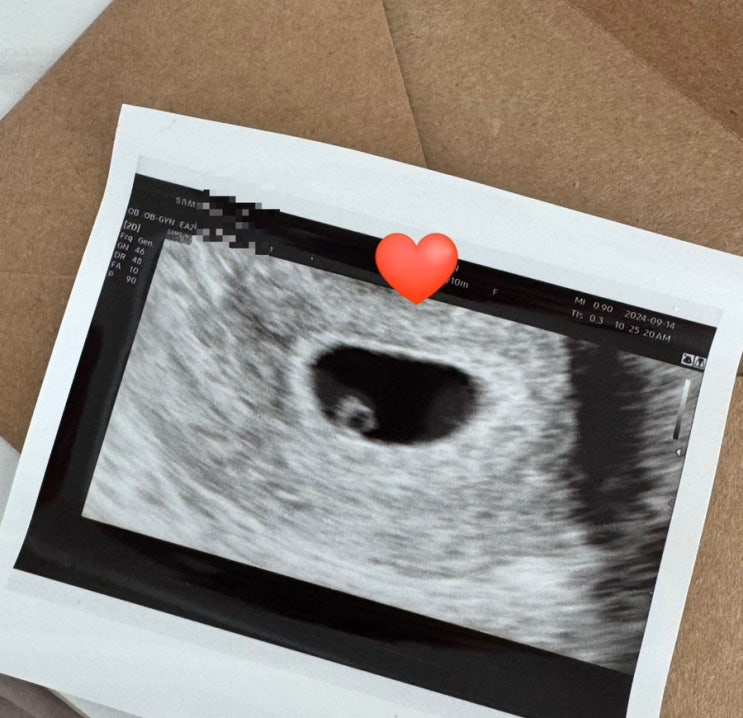

[임신일기] 임신9주차 일기 부정맥 갑상선기능저하 씬지로이드 복용 이슈폭팔9주차

이슈 폭팔한 임신 9 주차일기입니다 하하 9주차가 된지 하루쯤 지났을때 지난주 피검결과가 나왔다며 산부...

[임신일기] 8주차 일기 태아보험가입 입덧지옥탈출

태명은 쩰리 ! 설명하기 너무 길어서 패쓰 … 아직 인간의 모습이 아닌 쩰리 .. 그덕에 요즘 삶의 질이 매...

[임신일기] 임신6주차 - 7주차 일상 입덧지옥 입덧약후기 6주심장소리

안녕하세요 ~ 오늘은 임신 6주차와 7주차의 듬성듬성 일기모음입니다 일본 다녀온 일기도 올려야하는데 ^.^...